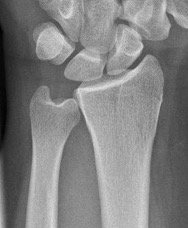

Ulna variance

Supination and pronation alter variance

- varies up to 3 mm with wrist position

- pronation increases ulnar variance

- supination decreases variance

90 / 90 view

- zero rotation view

- neutral supination / pronation

- PA film with wrist in neutral

- elbow 90° / shoulder abducted 90°

Line from lunate fossa and ulna head

- wide variation in population

- mean ulna variance is 1 mm (range 2 - 4)

Ulna neutral

Ulna positive

Ulna negative